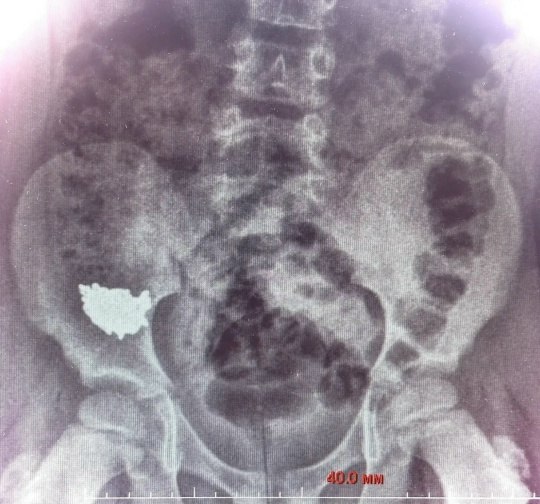

Ребенок проглотил украшение во время игры. На рентгеновском снимке медики увидели, что инородное тело находится в правой подвздошной области. Ребенка госпитализировали. Снимки на третьи и четвертые сутки после обращения показали, что цепочка не двигается по ЖКТ. Врачи решили провести срочную операцию из-за высокого риска перфорации кишки – образования отверстия в органе – и развития перитонита.